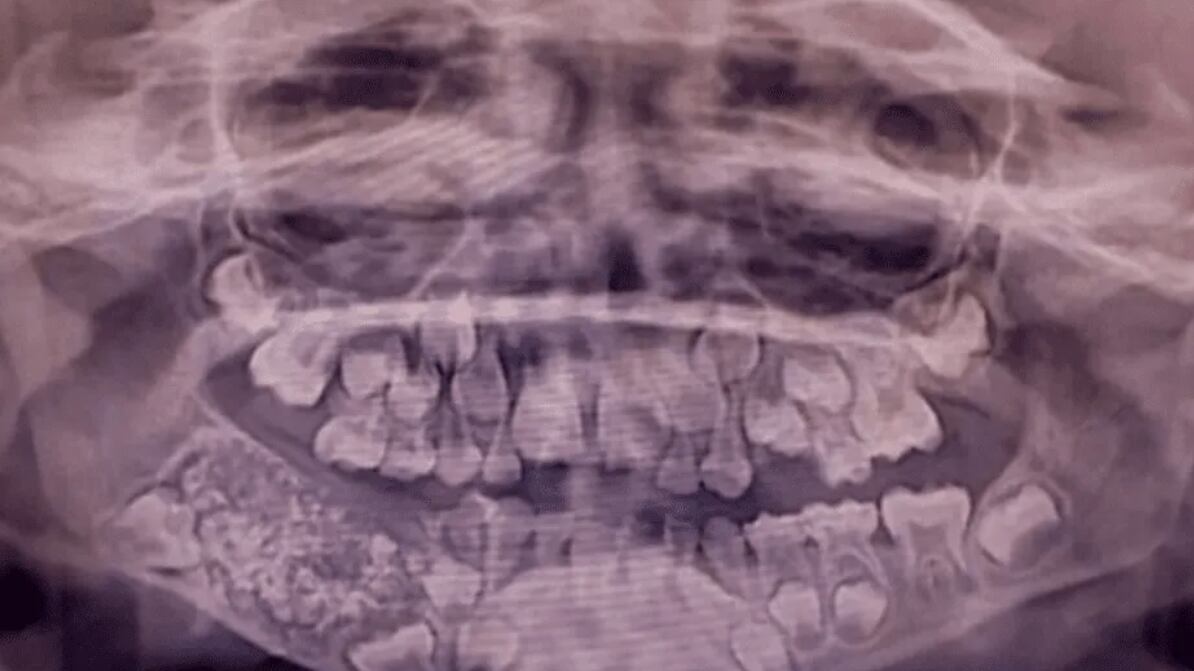

Con el tiempo, la masa continuó creciendo mientras que los dientes permanentes no brotaban en el área afectada. A los 7 años, las radiografías y tomografías revelaron una masa de aproximadamente 200 gramos alojada en la mandíbula. El Dr. Senthilnathan, responsable del Departamento de Cirugía Oral y Maxilofacial, identificó la anomalía como un “odontoma compuesto”, una variante benigna de tumor directamente relacionada con el desarrollo dental.

Durante la intervención, los cirujanos extrajeron una bolsa que contenía 526 dientes de dimensiones variables, desde apenas 0,1 milímetros hasta 15 milímetros de longitud. El proceso de clasificación y contabilización de cada pieza dental requirió cinco horas adicionales de trabajo meticuloso en el laboratorio.